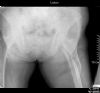

Hip Joint Ankylosis AP view - 50 Years post TB of the joint